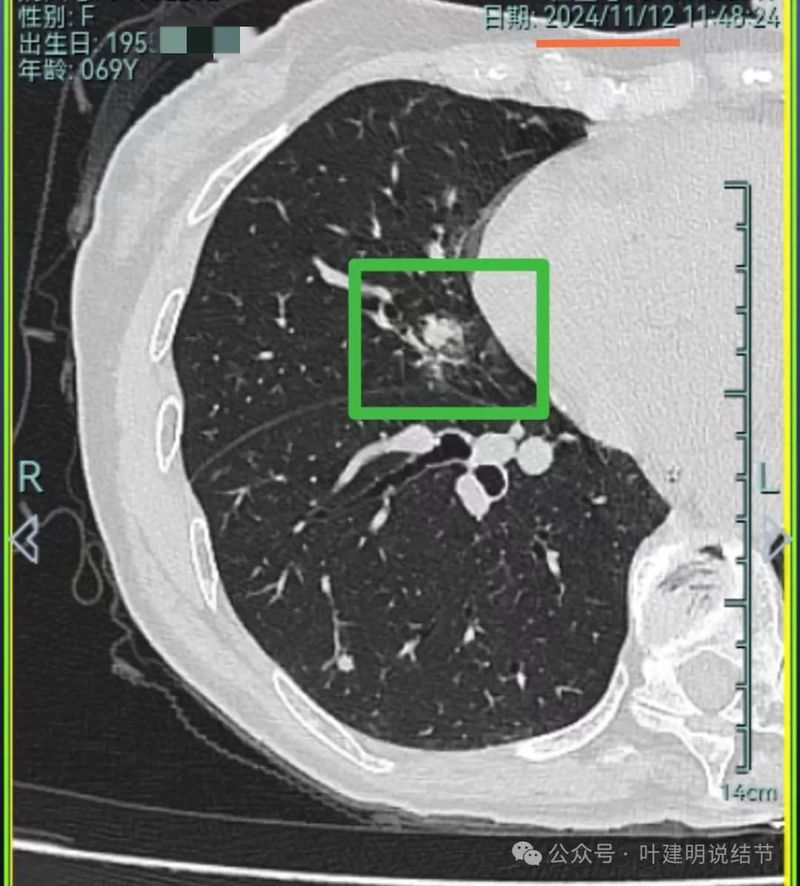

再看2024年11月复查的情况:

病灶5实性成分明显较前增多明显,总体上有进展,但这个病灶主要周围比较散,显得有些模糊。

我想我们这样也来考虑问题:1、左侧已经手术的确诊是肿瘤性质,左上已经消融的也是随访持续存在的磨玻璃密度结节,虽然没有病理依据,仍然要考虑广义上来讲的肿瘤范畴,看了以前的片子,从2019年到2023年并没有显著的进展,大概是肺泡上皮不典型增生可能性大。右侧的也有磨玻璃结节与混合磨玻璃结节考虑是肿瘤范畴的。所以总体上两肺多原发早期以磨玻璃为表现的肺癌,整体风险都不大。2019年切除的左肺下叶病灶也是纯磨玻璃密度,其实如果继续随访或者只做楔形切除也并没有什么关系。这说明体质本身或者致病的因素,就是容易长磨玻璃肺癌的,即便把目前发现的都解决,后续仍可能再有新的。原因不明,致病因素仍在。2、右肺上叶红色之处从2019年开始,是逐渐进展的,当然即便是现在,也不是说危险就已经很大,考虑仍然是原位癌或者微浸润性腺癌可能性大;中叶蓝色这处乍一看像至少是微浸润,但前后对比以后发现从2019年到现在,几乎没有显著进展,这样的话慢性炎伴肺泡上皮增生或者伴纤维增生也是有可能的,至少风险并不能认为大;右肺下叶黄色这一处,使纯磨玻璃密度,整体轮廓与边界清楚,考虑是肿瘤范畴的,不典型增生可能性较大,也有可能原位癌,随访稍有进展,风险仍然不大;中叶绿色这处是慢性炎伴钙化的,靠近叶裂的地方也像慢性炎,但此处随访有所进展。不过因为有卫星灶,整体显得比较散,所以虽然恶性可能性较大,但也不能完全除外炎性的可能性。当然如果此灶确实恶性,那风险则相对较其他进展缓慢的要高一些。从目前右侧所在的这些病灶来讲,真正有一定的风险而且最为确切的是红色这处,而且应该也没有到浸润性腺癌或者说不处理会要转移很危险这种程度。3、明确了多原发早期肺癌没有办法预防与控制,也明白了目前已经存在的较明显的这些病灶总体风险的高低。我们再来考虑需不需要近期干预处理。左侧既手术过又消融过,右侧的多发病灶目前又还没有到危险很高的程度,又没有办法预防后续再有新的病灶。我个人偏保守,我觉得仍然可以半年复查随访,如果最具风险的病灶有进展并且不处理可能导致不良后果,到这样的程度再来考虑综合如何处理干预便可。4、假如右侧我们予以处理,上叶红色的以及中叶蓝色的都可以楔切,但绿色考虑良性的再进展或以后像恶性时怎么办?而若中叶切除加上叶楔切,在左侧已经手术过的情况下肺功能影响相对也不小,何况右下比较中间的位置还有桔色这处呢。当然右下这处得考虑消融。所以,我的想法还是能熬再熬下,待其他监测有变化再通盘考虑。意见供参考!